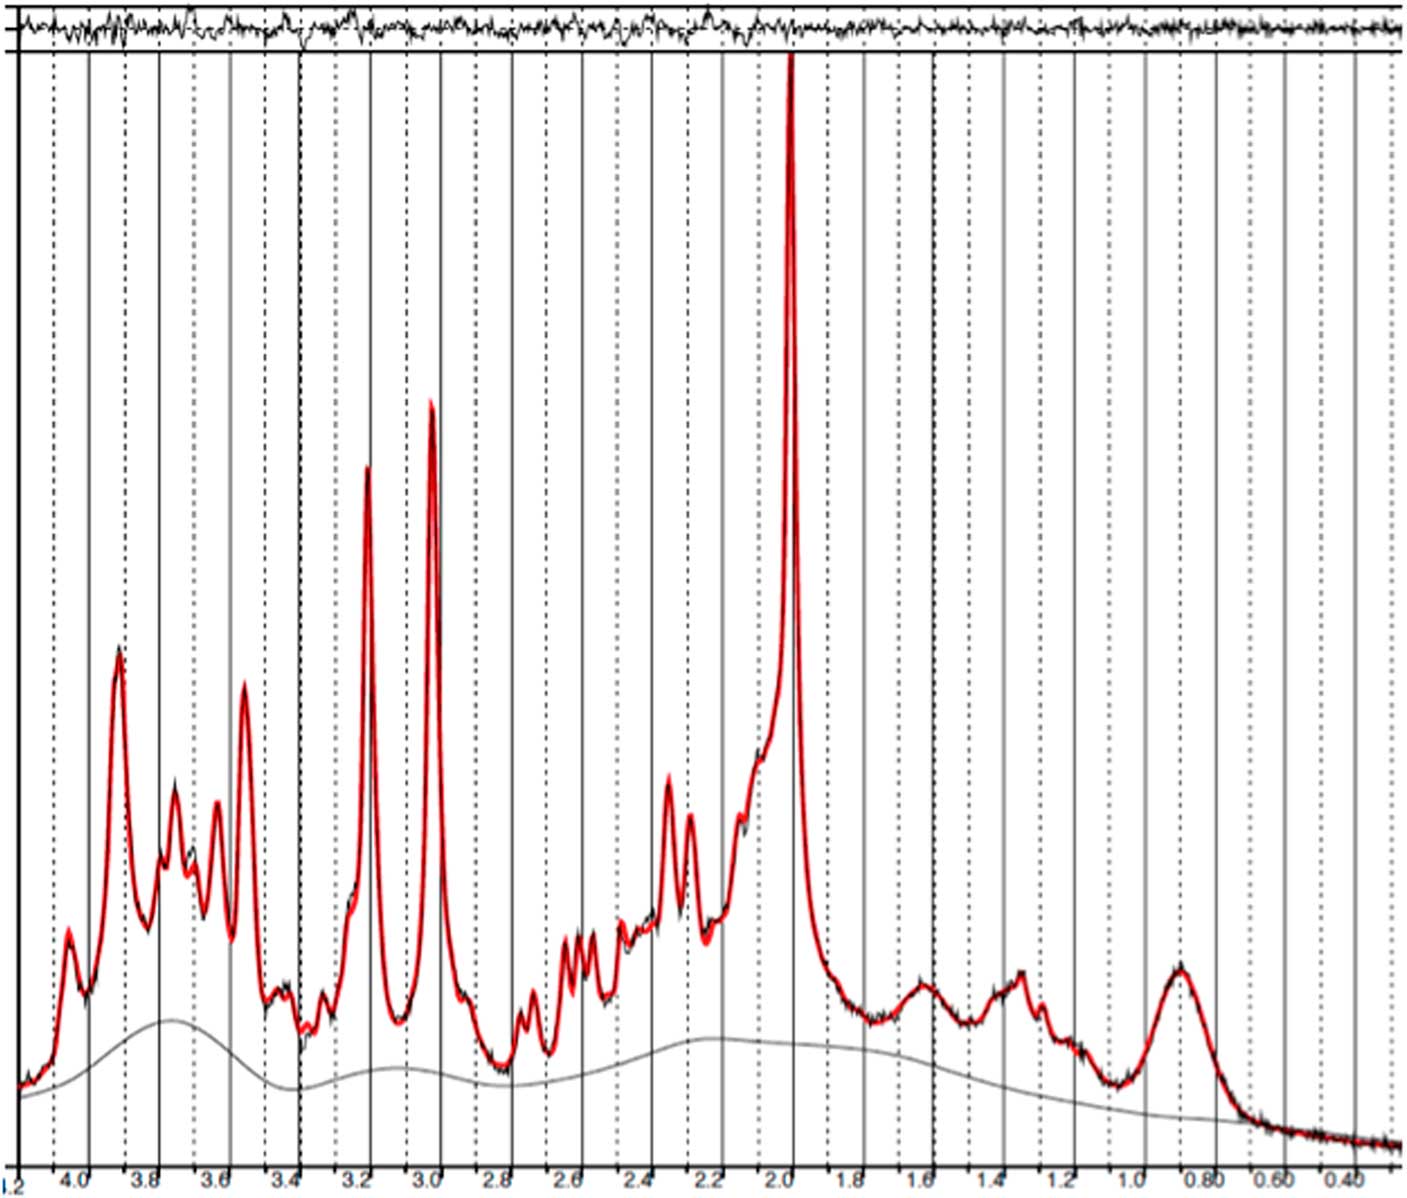

Baseline and follow-up data were collected from all 11 patients. However, prefrontal spectra from one patient (male) and one healthy subject (male) were discarded due to poor quality (CRLB>20%). Figure 2 illustrates representative spectra from PFC and Fig. 3 an individual plot for the GABA signal in PFC. No significant difference in prefrontal GABA levels was observed between patients pre-ECT (mean 0.248±0.04) and healthy subjects (mean 0.249±0.03), t(20)=0.089, p=0.93 (Fig. 4). To examine whether GABA/Cr ratios were affected by changes in creatine, we tested for significant differences in GABA/NAA ratios (p=0.92) and NAA/Cr ratios (p=0.99), but no significant difference was found. Diagnosis, that is bipolar disorder or MDD did not interact significantly with the GABA/Cr ratio (p=0.75). Moreover, we found no significant changes in GABA/Cr ratio after excluding patients receiving benzodiazepines.

Fig. 2 Example of a representative spectrum from the prefrontal cortex. The raw data are plotted as a thin black curve. The thick red curve is the LcModel fit to this data. The baseline is also plotted as a thin black curve. At the top are plotted the residuals.